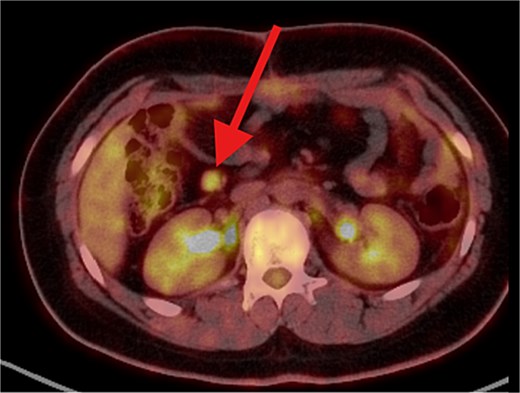

The patient underwent left lateral hepatectomy and cholecystectomy following diagnosis. Histopathology confirmed undifferentiated embryonal sarcoma (UES) of the liver with a 1 mm clear margin (Fig. 1); immunohistochemistry supported the diagnosis. The gallbladder showed chronic cholecystitis, and the lymph nodes were tumor-free. Postoperative imaging after two months revealed a recurrent mass near the stomach (Fig. 2), confirmed as recurrent UES by biopsy. Re-excision showed extensive necrosis and peritoneal infiltration. Positron emission tomography – computed tomography (PET-CT) later identified peritoneal and mesenteric metastases (Fig. 3). Follow-up PET-CT also revealed multiple small hypermetabolic hepatic nodules in addition to peritoneal and mesenteric lesions, indicating intrahepatic disease recurrence. Six cycles of chemotherapy resulted in near-complete resolution of metabolic lesions, with minimal residual activity. Follow-up imaging showed near-complete resolution of hepatic nodules, with only one residual, non-suspicious tiny nodule. After additional chemotherapy and targeted therapy cycles, PET-CT revealed new focal hypermetabolic activity near the splenic flexure, anterior to the spleen, raising concern for recurrence (Fig. 4). The patient underwent omentectomy and splenectomy. Histopathology confirmed metastatic UES in a 2.5 cm splenic lesion with hemorrhage and necrosis, and a 0.4 cm omental nodule, both completely excised. A total of 15 chemotherapy cycles were completed. Post-treatment imaging showed a mixed-density lesion in the splenic bed with FDG uptake, possibly post-surgical, and a new hypermetabolic mesenteric nodule (Fig. 5). Magnetic resonance imaging showed a cystic post-surgical collection without enhancing lesions. Subsequent imaging revealed regression of the splenic bed lesion and resolution of the mesenteric nodule; however, a new hypermetabolic mesenteric density emerged (Fig. 6). The lesion was placed under active surveillance, with additional chemotherapy administered and repeat imaging scheduled to assess response. Bilateral axillary lymph nodes showed reactive hypermetabolism. The patient, having undergone hepatectomy, splenectomy, and multimodal therapy, remains under close surveillance with encouraging treatment response.

PET/CT scan showing a clear surgical bed. Almost complete metabolic resolution of the previous hypermetabolic abdominal deposits. Development of focal hypermetabolic activity just anterior and abutting the lower spleen pole, at the projection of splenic flexure of the descending colon, this lesion is nonspecific.